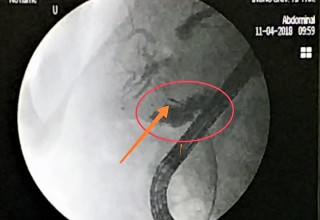

Microwave antenna in bile-duct

The doctors applied microwave energy to destroy tumor growth prior or post bile-duct stent installation to reestablish and maintain normal bile flow. The microwave energy is applied to the tumors in and around the duct and stent with percutaneous transhepatic cholangiography (PTC) using fluoroscope (real-time x-ray) images of liver, bile-ducts and gallbladder-ducts. A long flexible needle-catheter is inserted into the liver under fluoroscopy to locate and identify blockages using contrast dye. Once the blockage is identified, a smaller diameter catheter with microwave antenna is introduced into first catheter, the antenna is positioned along the duct and the microwave energy is applied using preset temperature and time durations. The antenna is retracted along the duct and the energy application is repeated until the desired length of the duct is treated. The doctors would remove the microwave catheter and verify bile-duct flow with fluoroscopy. The microwave energy application is controlled with direct temperature feedback from the ablation antenna during the procedure to ensure safety and efficacy.